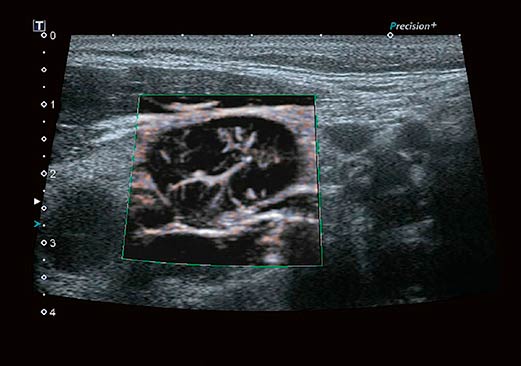

Технология визуализации микроциркуляторного русла (SMI), разработанная корпорацией Canon Medical Systems, расширяет диагностические возможности ультразвуковых систем Aplio. Позволяет визуализировать низкоскоростной кровоток в микрососудах.

Технология Advanced Dynamic FlowTM (ADF) обеспечивает высочайшее пространственное разрешение в режиме цветового допплеровского картирования, позволяя с высокой точностью и детализацией выявлять мелкие сосуды и зоны со сложным характером кровотока, в полной мере сохраняя качество изображений, присущее B-режиму.

Цветовая энергетическая ангиография сочетает чувствительность и глубину проникновения энергетического допплера с информацией о направлении кровотока, полученной при цветовом допплеровском картировании, позволяя более точно определять сосудистый рисунок ткани.

Технология визуализации микроциркуляторного русла (SMI), разработанная корпорацией Canon Medical Systems, расширяет диагностические возможности ультразвуковых систем Aplio. Позволяет визуализировать низкоскоростной кровоток в микрососудах.